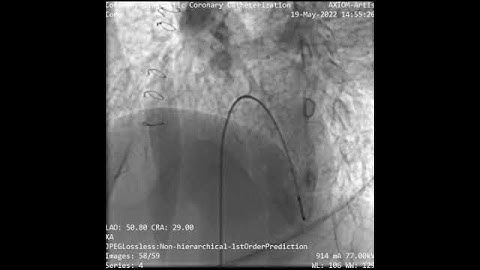

LV Angiogram Profiling Perimembranous VSD